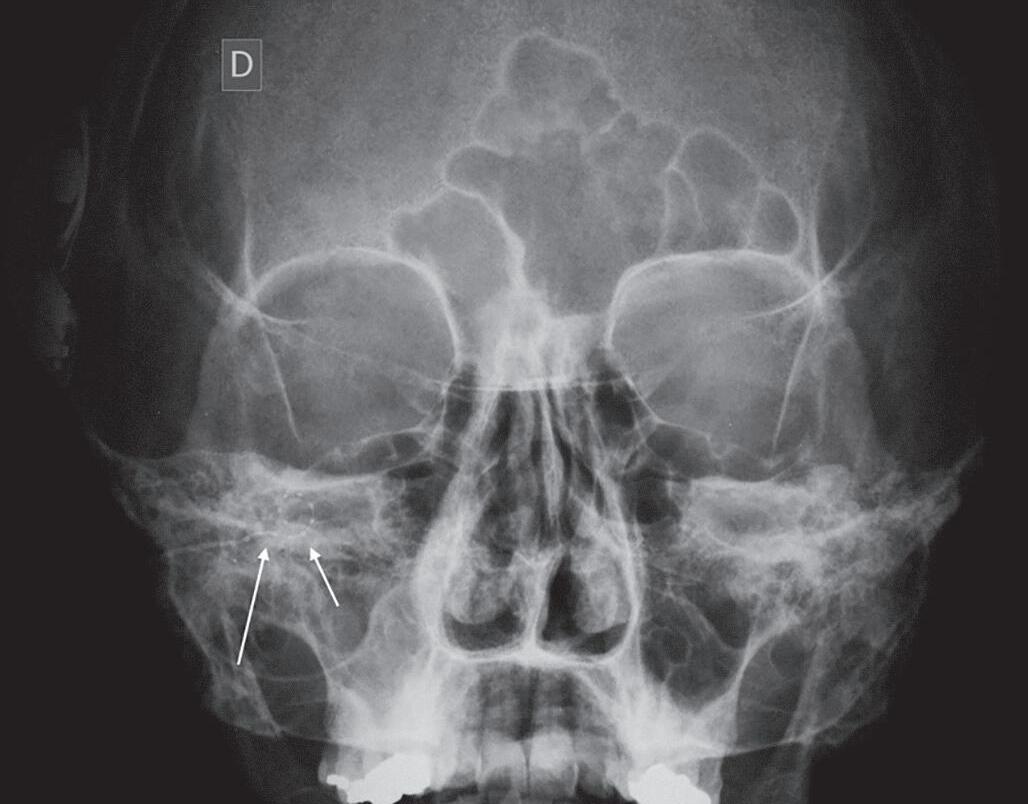

Raios X do Osso Temporal Indicação

A avaliação radiográfica do osso temporal é realizada pelas incidências de Stenvers, Schuller e transorbital. Teve maior aplicação no passado antes do advento da tomografia computadorizada (TC). Atualmente, sua aplicação é limitada, sendo utilizada no controle do posicionamento do implante coclear no centro cirúrgico e, raramente, ambulatorialmente.

Incidência de Stenvers: nesta incidência, o feixe de raios X é posicionado 45o em relação ao osso temporal. Era usada para demonstrar o osso petroso, meato acústico interno e labirinto ósseo (Fig. 1-1). Uma projeção semelhante pode ser obtida por reconstruções tomográficas multiplanares.

Incidência de Schuller: nesta incidência, o plano sagital da cabeça é paralelo ao feixe de raios X que é projetado 25o a 30o na orientação cefalocaudal, evitando a sobreposição das mastoides. Era utilizada para demonstrar o osso petroso, o meato acústico interno e labirinto ósseo.

Incidência transorbital: a incidência transorbital é uma visão frontal da mastoide e pirâmide petrosa, obtida com a cabeça do paciente fletida, até que a linha orbitomeatal fique perpendicular à mesa de estudo. Era usada para demonstrar os condutos auditivos internos.